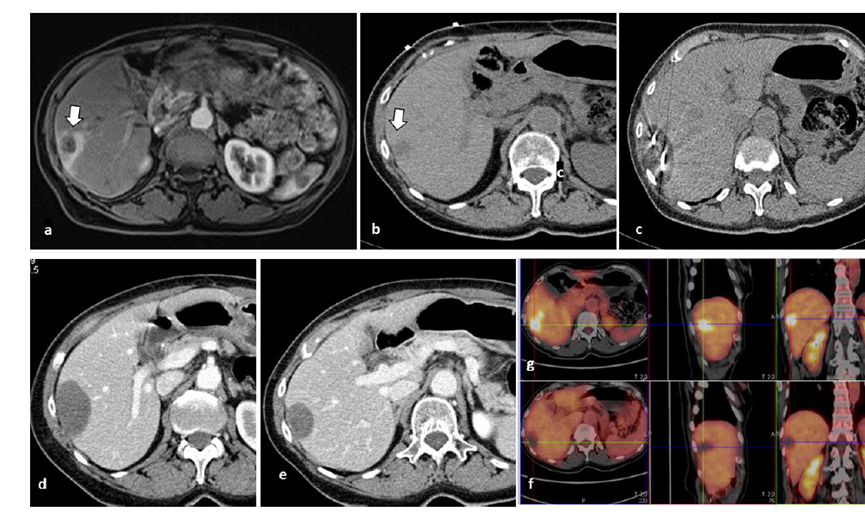

冷凍消融膽囊附近腫瘤病灶

(A)動脈期 MRI 顯示膽囊附近有外周增強病變(箭頭)。

(B)手術(shù)過程中 CT 顯示冷凍探針位于病灶內(nèi)。

(C)消融后,術(shù)后 1 個月CT 顯示完全消融(箭頭)。

(A)動脈期CT圖像顯示有一個包膜下結(jié)節(jié)(箭頭)。(B)門靜脈期CT圖像顯示病灶區(qū)(箭頭)。(C) 在手術(shù)過程中的CT顯示一個冷凍探針位于病灶內(nèi)。(D)消融后,術(shù)后1個月影像CT顯示完全消融。患者在手術(shù)及住院期間無并發(fā)癥及重大并發(fā)癥發(fā)生。隨訪時間中位數(shù)為7個月(范圍:3-12個月),隨訪期間患者無局部腫瘤進展或死亡。

技術(shù)成功率為100%,本研究中77.8%(7/9)的患者達到了完全消融,輔助局部治療后,所有患者均完全消融。

膽囊附近轉(zhuǎn)移灶(來自子宮頸癌)的冷凍消融術(shù)(A)門靜脈期 CT 圖像顯示膽囊附近有病變(箭頭)。(C) 手術(shù)過程中CT 顯示冷凍探針位于病灶內(nèi)。(D)消融手術(shù)后 1 個月CT 顯示完全消融。